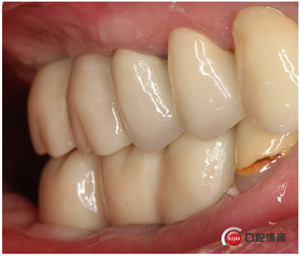

再看看是不是效果好多了?哼!我就是個(gè)較真兒的人。

好了,別貧了。病例也展示完了,大家眼睛亮著呢,一看這方法就靠譜,一看就知道這是最棒的方法是不是?